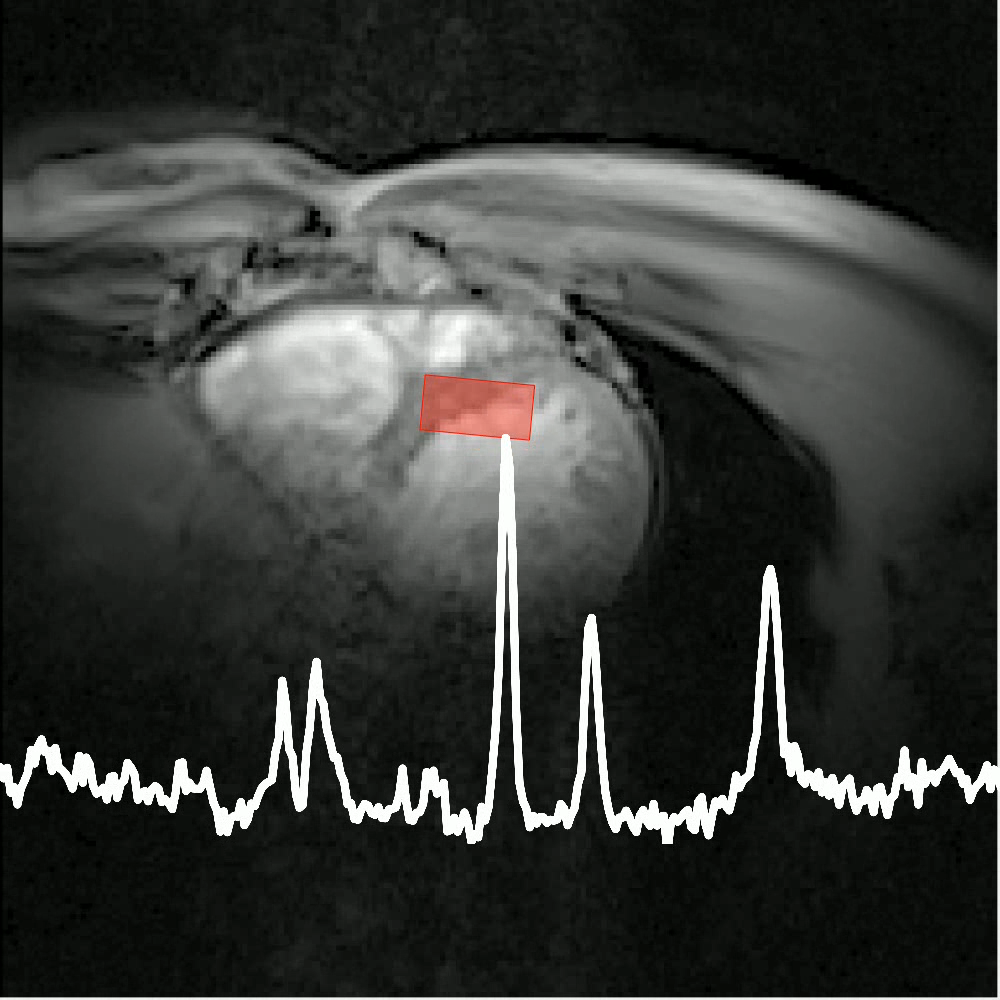

Visualisation of high energy phosphate signal changes as the heart beats.

The heart is responsible for keeping us going and thereby consumes considerable energy itself. As a pump, and being situated in between the lungs, it is constantly in motion, which poses challenges to imaging and to capturing its metabolism by MRS. Cardiac energetics and respiratory motion are therefore our current central topics of investigation.

Here we apply our expertise of studying skeletal muscle metabolism. The thin layer of myocardium enclosing the ventricles imposes challenges in SNR and in separating the signals. We use multi-nuclear interleaving for image-navigated ³¹P MRS to improve localisation accuracy.